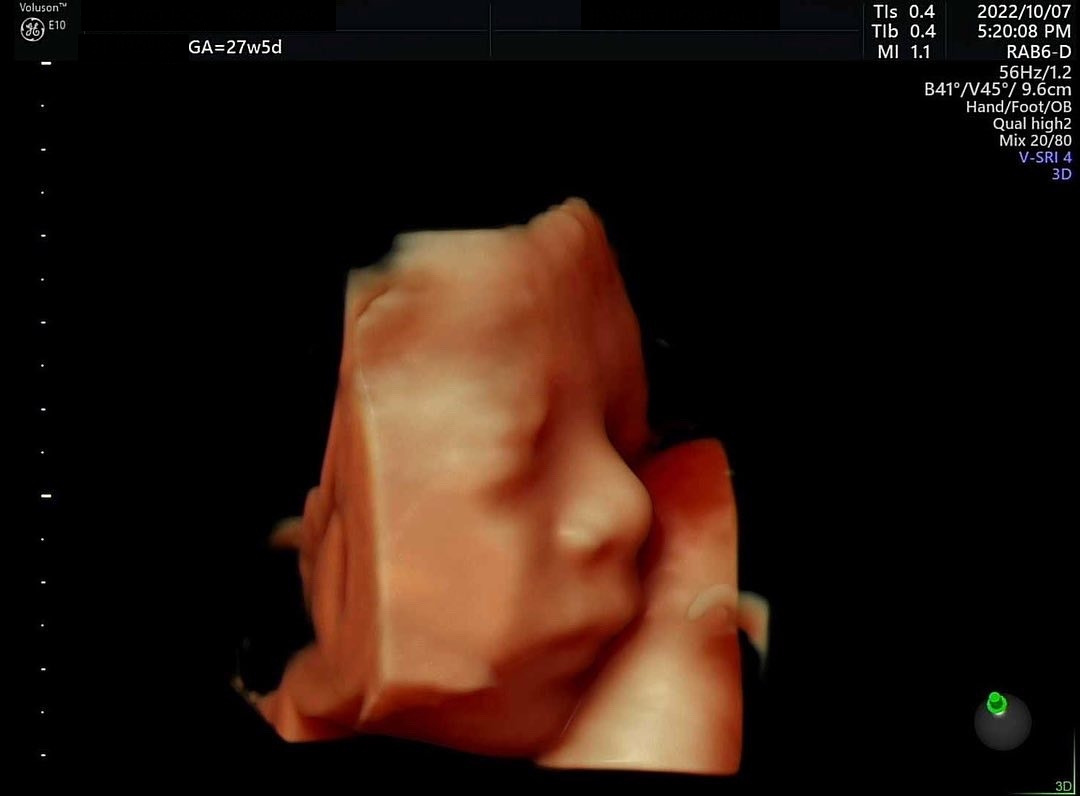

3차 시도 때는 아기가 팔을 내렸다. 그 대신 태반에 얼굴을 파묻고 있었는데, 내가 왼쪽으로 돌아누우니 얼굴과 태반 사이에 공간이 조금 생겨 사진을 찍을 수 있었다. 오똑한 코와 통통한 볼이 너무 예쁘다. 특히 우리가 초음파 사진을 보고 아빠를 닮았다고 확인했던 코 모양은 입체로 보아도 정말 아빠를 똑 닮았다. 작고 소중한 우리 아기, 엄마가 조금 귀찮게 해서 미안해! 그래도 얼굴 보여줘서 고마워♥

아빠를 똑 닮은 코, 특히 콧볼... 오른쪽은 양수를 먹고 있을 때 찍혀 입모양이 너무 귀엽다.